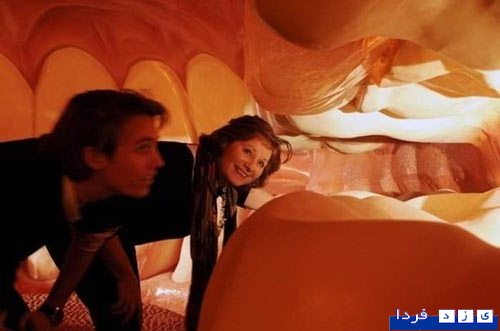

این ساختمان در هلند ساخته شده و با سفر به درون آن میتوان با بازدید از همه بخشها، از کارکرد درست یک بدن سالم آگاه شد و آموزش دید. ارتفاع این ساختمان که از نظر ظاهری پیکر انسانی نشسته است، 35 متر است.

این تصاویر عجیب و بی نظیری كه مشاهده می کنید مربوط به یك ساختمان واقع در كشور هلند است كه شبیه انسان ساخته شده و از تاریخ چهاردهم مارس 2008 برای بازدیدكنندگان فعال بوده است. بطوریکه با سفر به درون آن میتوان از تمامی قسمت ها و کارکرد درست یک بدن انسان سالم اطلاعات لازم را کسب کرد و در این تجربه جدید برای بازدیدكنندگان خصوصا دانشجویان رشته پزشکی این امکان فراهم شده بود تا با قسمتهای داخلی بدن انسان و نحوه فعالیتهای آنها از نزدیك آشنا شوند.

این بنای انسانی که از نظر ظاهری پیکر انسانی نشسته است، در كنار یك ساختمان شیشه ای با ارتفاع 35 متر بنا شده كه در جوار اتوبان A44 آمستردام به هاگو (Hague) قابل مشاهده است. گرچه این تصاویر شاید برای شما دوستان پرشین استار چندان جدید نباشد ولی آنچه مهم است اهمیت آموزش و ایجاد انگیزه برای سهولت در شناخت و درک بهتر ساختمان پیچیده و اسرار آمیز بدن انسان نسبت به نیاز محققین و دانش اندوزانی است که مایلند به گوشه ای از اسرار عظمت خلقت خداوند که همان اشرف مخلوقات است دست یابند.